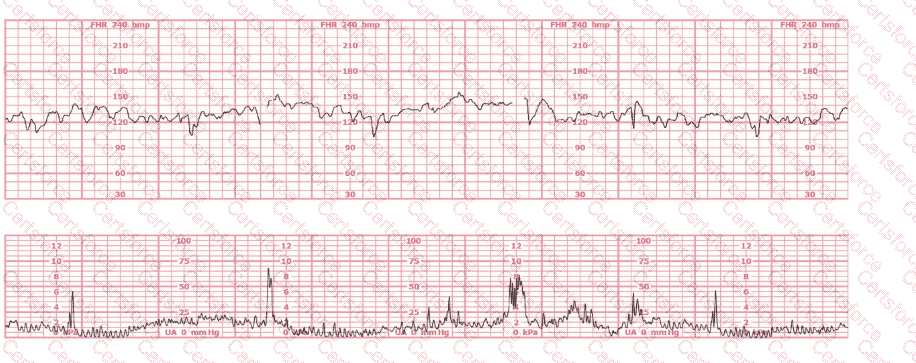

The baseline fetal heart rate in this tracing is:

Question # 2

155 beats per minute

Indeterminate

Tachycardia